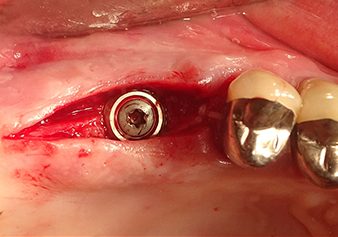

Situation after insertion of the implant

Fig.9: Situation after insertion of the implant (length: 10 mm, prosthetic platform: 6.5 mm) immediately before suturing.